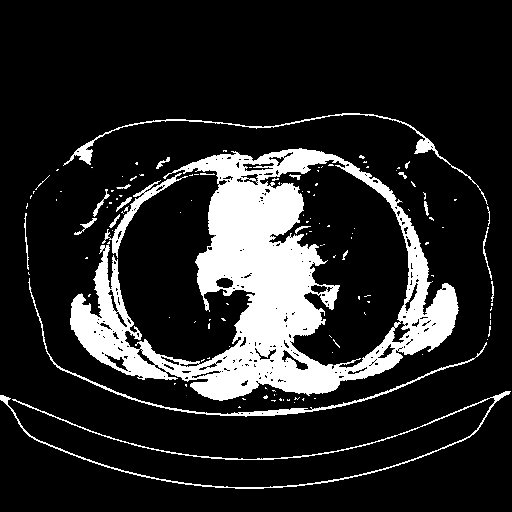

Reconstructed NATIVE CT scan (cycle consistency)

Full window (WL 1023.5, WW 4095 β†’ Low βˆ’1024, High +3071)

Actual HU range: [-1024.0, 3071.0]